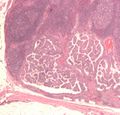

اسم سرطان الغدة الدرقية الحيمي مشتق من الحليمات الموجودة في خلاياه السرطانية، والتي تُرى تحت المجهر. وتتضمن الخصائص المميزة:

- Characteristic Orphan Annie eye nuclear inclusions (nuclei with uniform staining، التي تظهر فارغة بسبب الكروماتين ومساحيق النوى[11] and psammoma bodies on light microscopy. The former is useful in identifying the follicular variant of papillary thyroid carcinomas.[12]

Micrograph of papillary thyroid carcinoma demonstrating prominent papillae with fibrovascular cores. H&E stain.